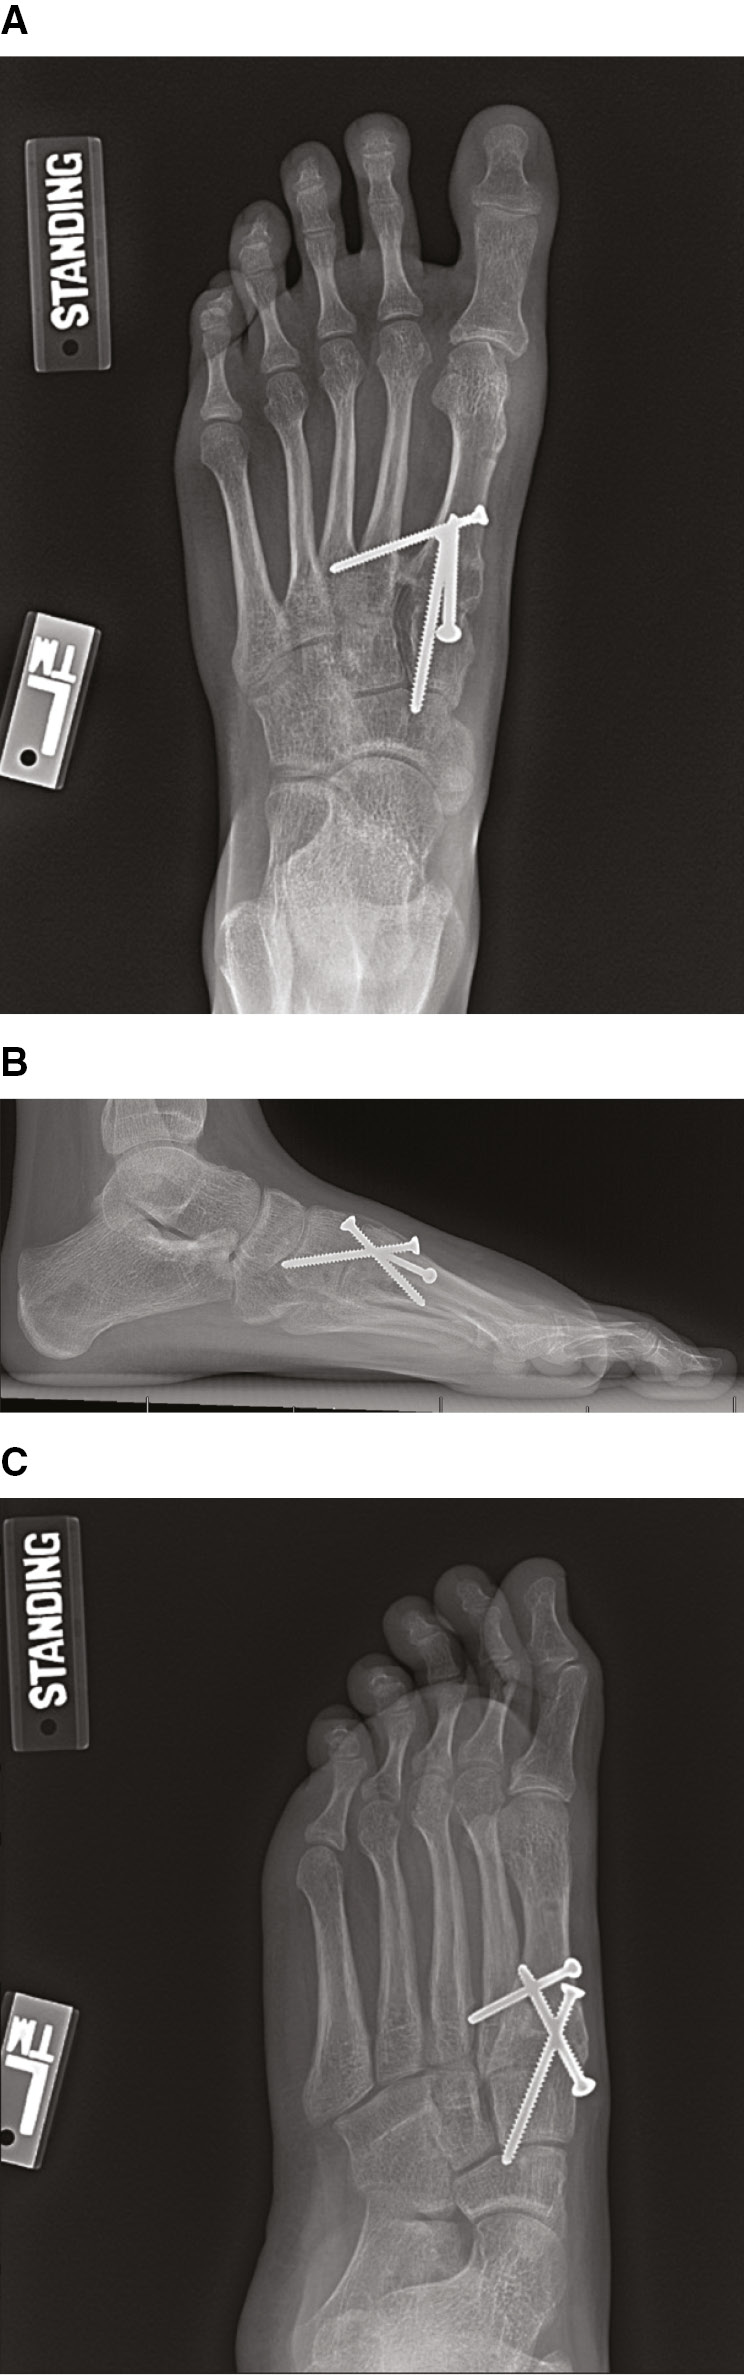

The patient is placed in a short leg splint with bunion dressing per surgeon’s preference. Non-weight-bearing is recommended for 6 weeks postoperatively. At the first postoperative visit, sutures are removed, and the patient is placed into a tall cast boot with a removable bunion splint. At six weeks, X-rays are obtained, and weight-bearing is initiated. The authors do not use X-rays to adjust weight-bearing status in the setting of nonunion or delayed union. However, if provider concern exists, additional protection can be considered by keeping the patient in a boot for a longer period. Once the patient is comfortable fully weight-bearing in the boot, they may wean into a regular shoe. The patient is then seen at 3 and 6 months postoperatively for radiographic and clinical assessment (Figure 8). Implant removal is not routinely performed unless the hardware becomes symptomatic.

Figure 8. Six-week postoperative AP (A), lateral (B), and oblique (C) radiographs of patient from Figure 1 demonstrating successfully maintained correction of hallux valgus.